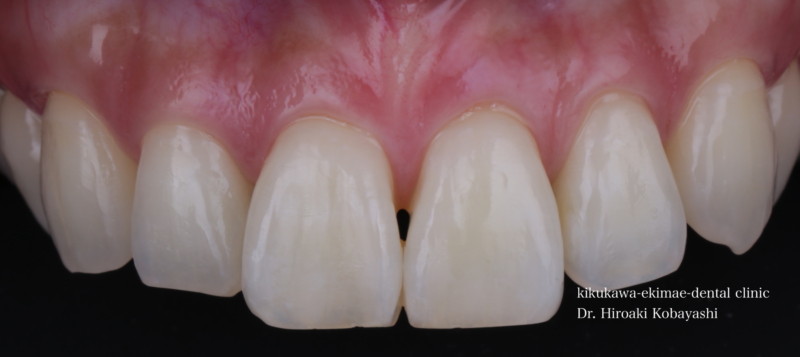

歯並びを気にされて来院されました。見た目改善を目的にワイヤーによる部分矯正を希望されました。 ブラケット装着用のマウスピースを作り、ブラケット装着を行います。   弱い力をかけながら、ワイヤーにより歯を動かします。強い力を急にかけると歯の根が吸収されてしまいます。なので弱い力で歯を動かすことによって根への負担が少なく歯根吸収のリスクが少なくなります。               6ヶ月程度で歯の並びを改善することができました。   before after